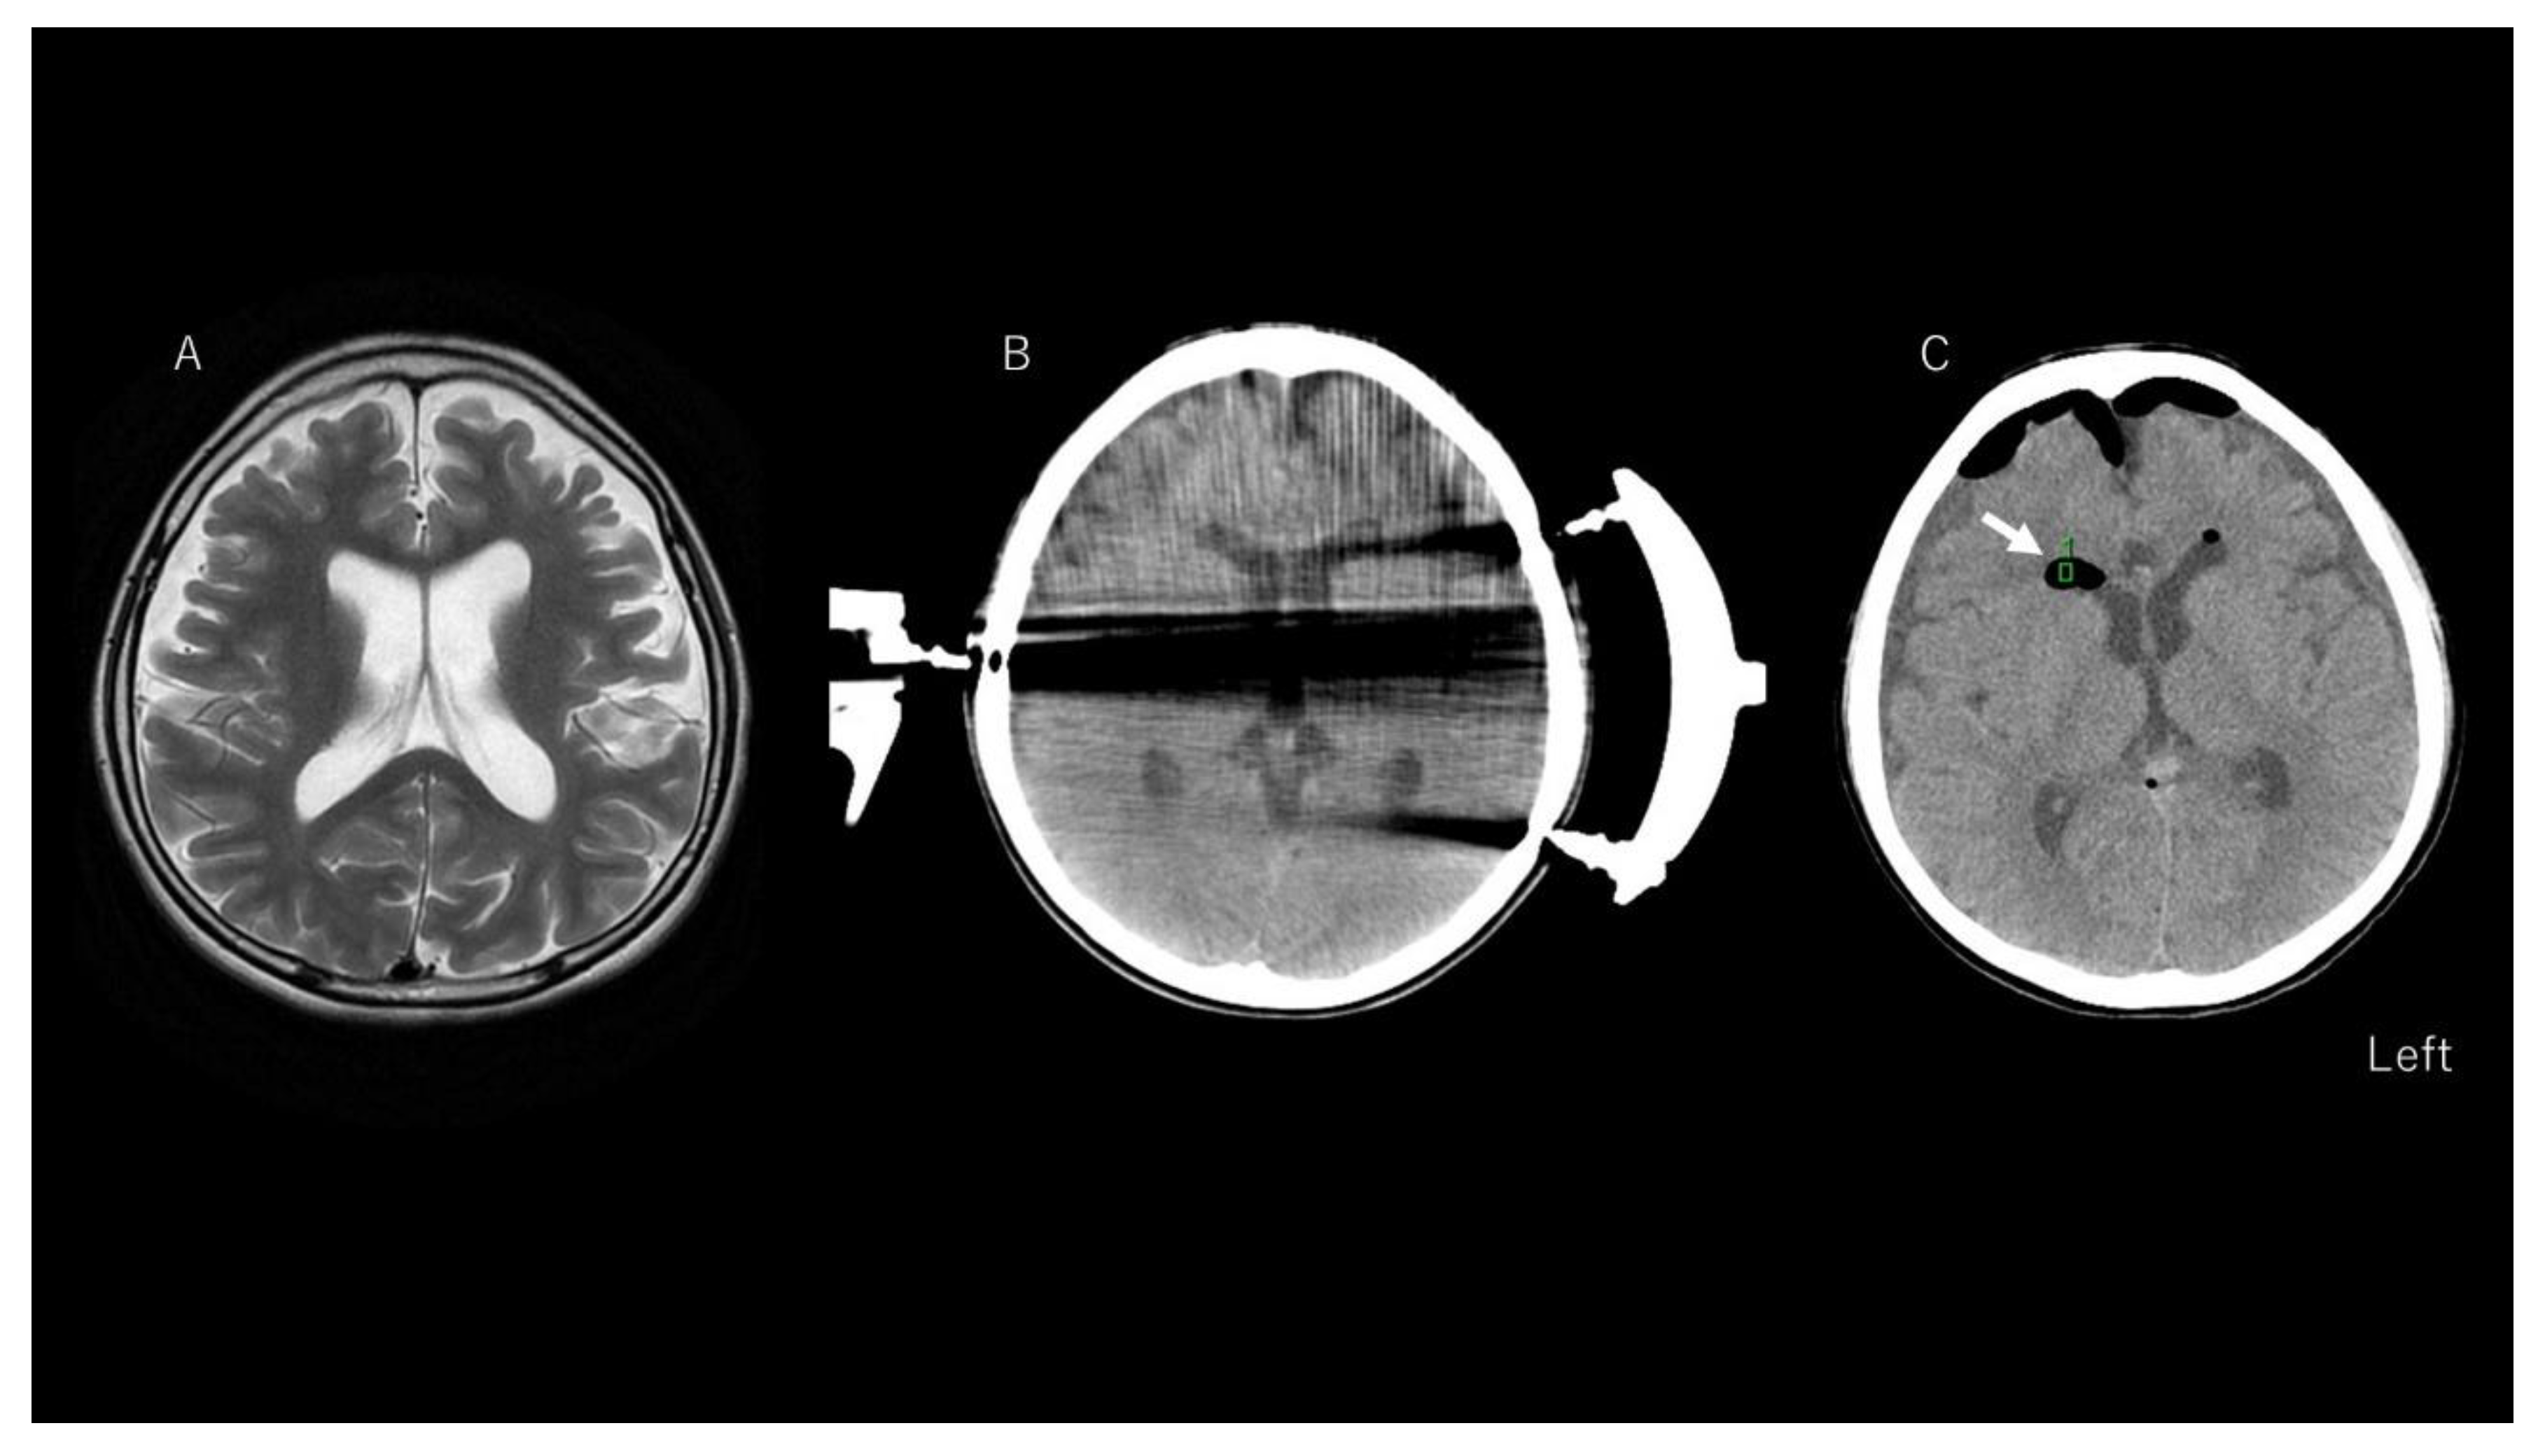

3.3. Representative Case of Chemical Meningitis